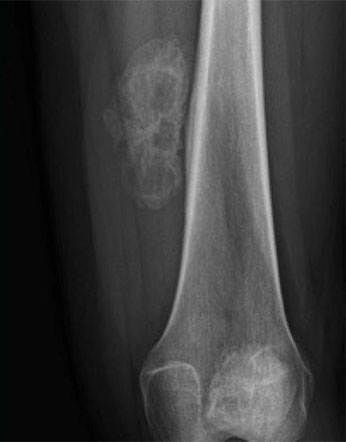

Bone tumors are rare lesions. A large part of these tumors are benign lesions, and they often occur by chance during radiological examinations for another reason. As a complaint, they usually show swelling and pain. Rarely, it is diagnosed after causing a fracture in the place where it was. Osteoid osteoma, osteochondroma (exostosis), enchondroma, non-ossifying fibroma, eosinophilic granuloma, simple bone cyst, fibrous dysplasia and intraosseous lipoma/ganglion are the most common lesions of benign tumors.